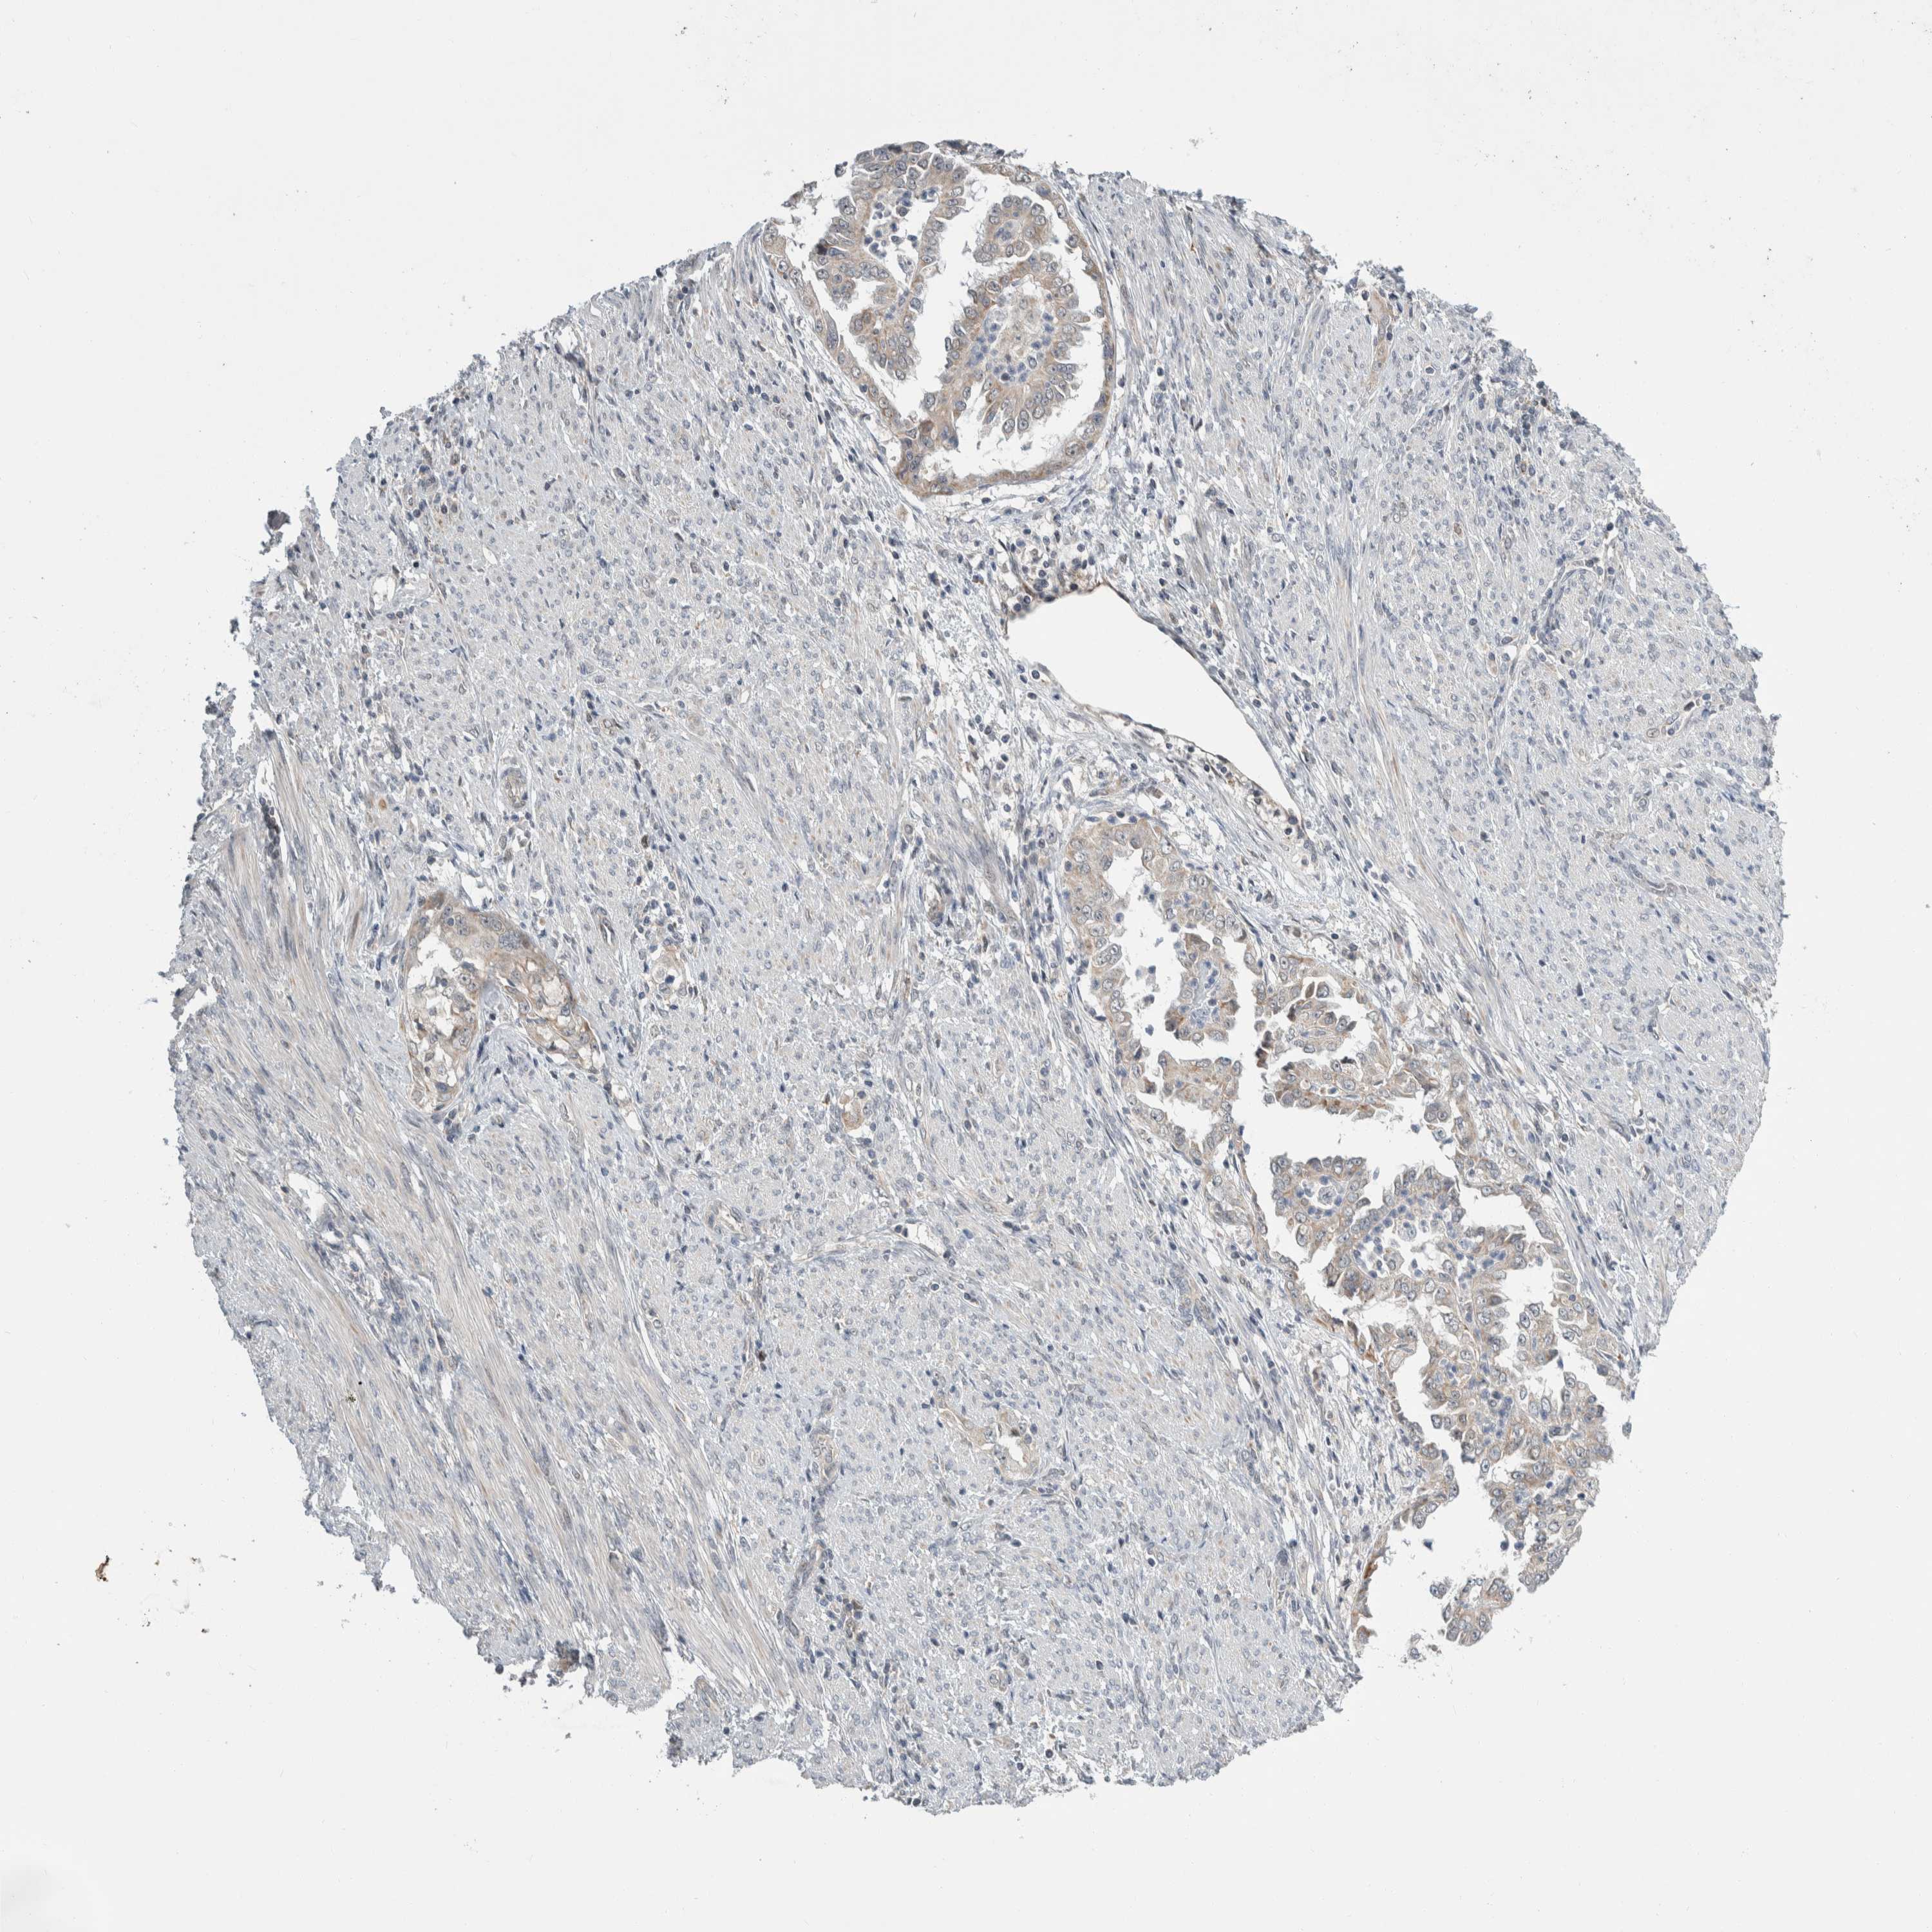

ENDOMETRIAL CANCER - Protein expressioni

A mouse-over function shows sample information and annotation data. Click on an image to view it in a full screen mode. Samples can be filtered based on level of antibody staining by selecting one or several of the following categories: high, medium, low and not detected. The assay and annotation is described here.

Note that samples used for immunohistochemistry by the Human Protein Atlas do not correspond to samples in the TCGA dataset.

Antibody stainingi

Antibody staining in the annotated cell types in the current human tissue is reported as not detected, low, medium, or high, based on conventional immunohistochemistry profiling in selected tissues. This score is based on the combination of the staining intensity and fraction of stained cells.

Each image is clickable and will lead to virtual microscopy that enables deeper exploration of all samples and also displays staining intensity scores, fraction scores and subcellular localization as well as patient and tissue information for each sample.

Antibody HPA024361

Antibody HPA064939

Staining

High

Medium

Low

Not detected

Intensity

Strong

Moderate

Weak

Negative

Quantity

>75%

75%-25%

<25%

None

Location

Nuclear

Cytoplasmic/membranous

Cytoplasmic/membranous,nuclear